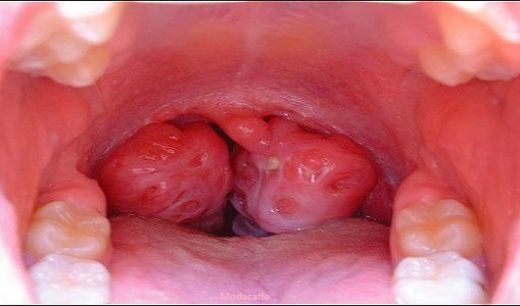

Sol bademcik şişmesi, genellikle boğazın arka kısmında yer alan lenfoid dokunun iltihaplanması veya enfekte olması durumudur. Bademcikler, bağışıklık sisteminin bir parçası olarak, vücut savunmasında önemli bir rol oynamaktadır. Bu durum, çeşitli etkenlerden kaynaklanabilir ve genellikle enfeksiyon belirtisi olarak ortaya çıkar.

Sol bademcik şişmesi, çeşitli belirtilerle kendini gösterebilir. Bu belirtiler şunları içerebilir: - Ağrı veya rahatsızlık hissi: Şişen bademcik, yutkunma sırasında ağrıya neden olabilir.

- Yutma zorluğu: Bademciklerin büyümesi, yiyeceklerin yutulmasını zorlaştırabilir.

- Boğazda tahriş: Şişmiş bademcikler, boğazda gıcırtı veya kaşıntı hissi yaratabilir.

Sol bademciğinizin şişmesi ve yutkunma zorluğu yaşamanız, genellikle bademcik iltihabı ile ilişkilendirilebilir. Bademciklerin iltihaplanması, çevresindeki dokulara da etki edebileceği için kulak ağrısı gibi belirtiler ortaya çıkabilir. Bu durum, bademciklerin ve çevresindeki lenf dokularının iltihaplanması sonucu gelişir.